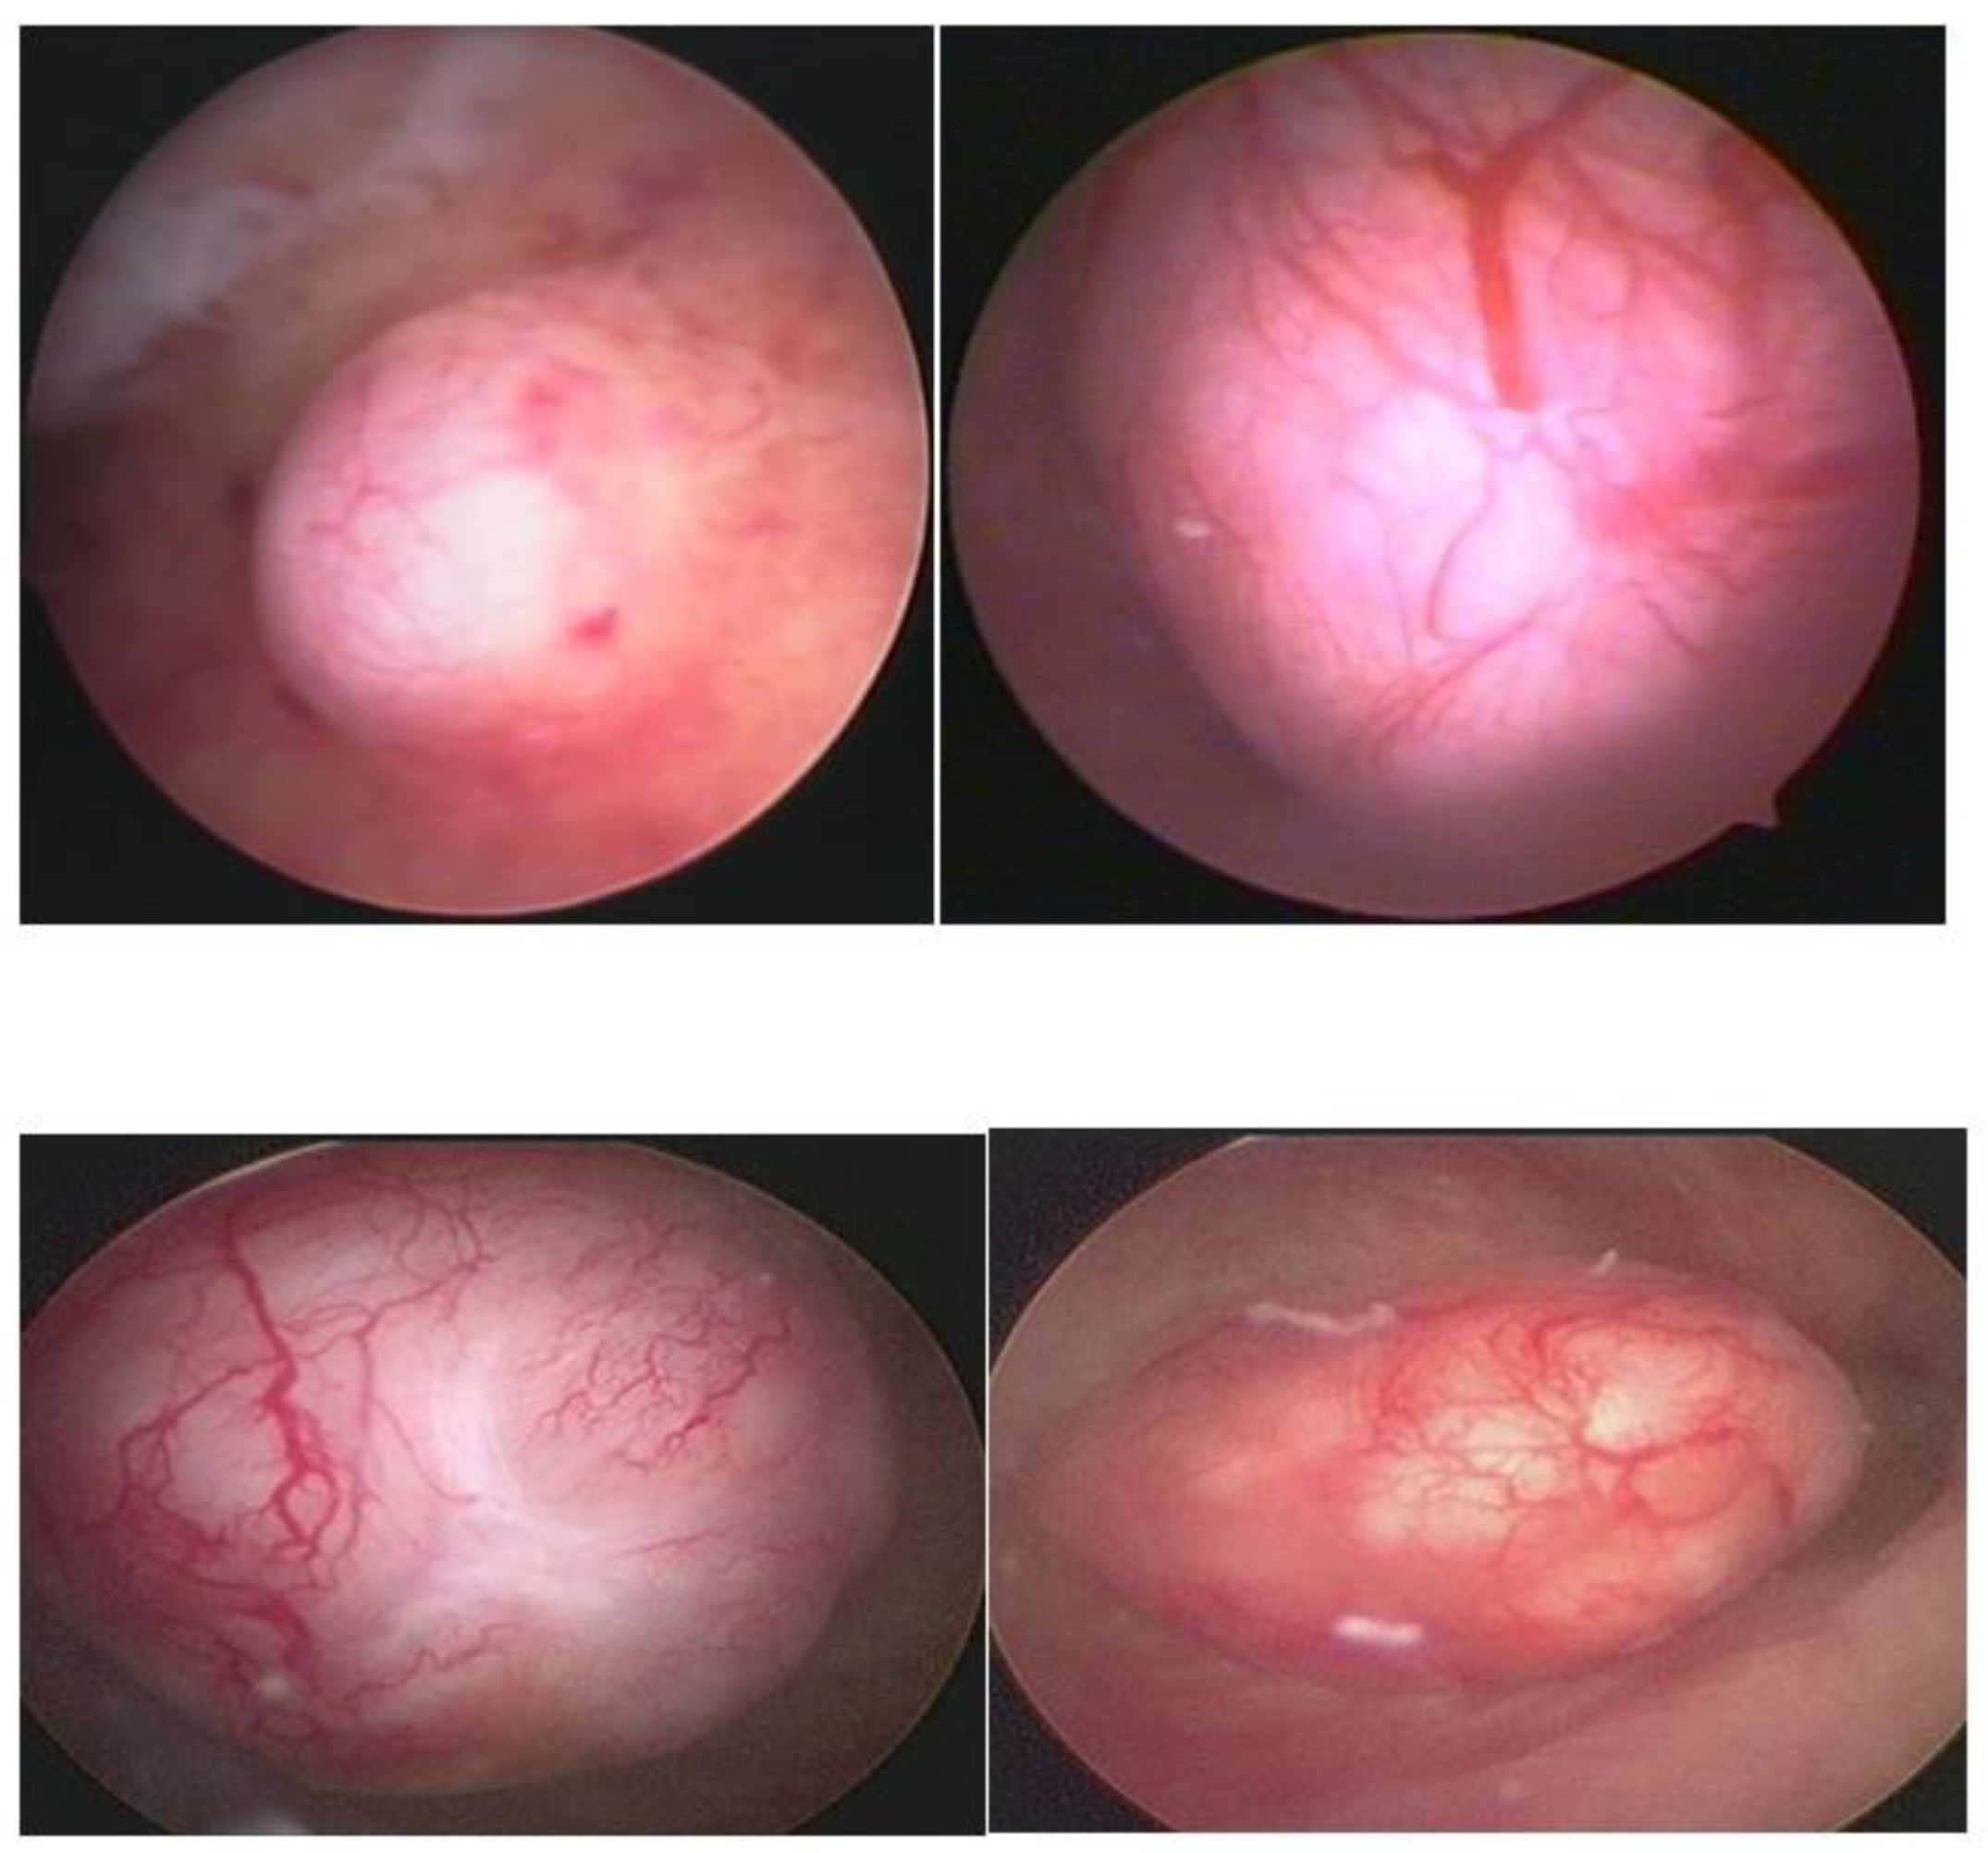

In our service, the most performed technique is using the 5 Fr tweezers or scissors. Initially, the endometrium is incised around the nodule until accessing the plane of the pseudocapsule; then, with the forceps or the body of the hysteroscope, entering between the nodule and the myometrium, the release is initially performed, laterally first and then centrally, until its complete release (Figure 7).

At the end, the nodule will be loose in the cavity and can be fragmented or completely removed with grasping forceps. In cases of difficulty in removing the nodule from the cavity, the patient should be instructed to return in 7 to 10 days, during which time either the nodule will be spontaneously expelled by the patient—she should be oriented about this possibility—or it will have drastically decreased in size, allowing its removal.

Figure 7. Office hystreroscopic myomectomy with scissor.